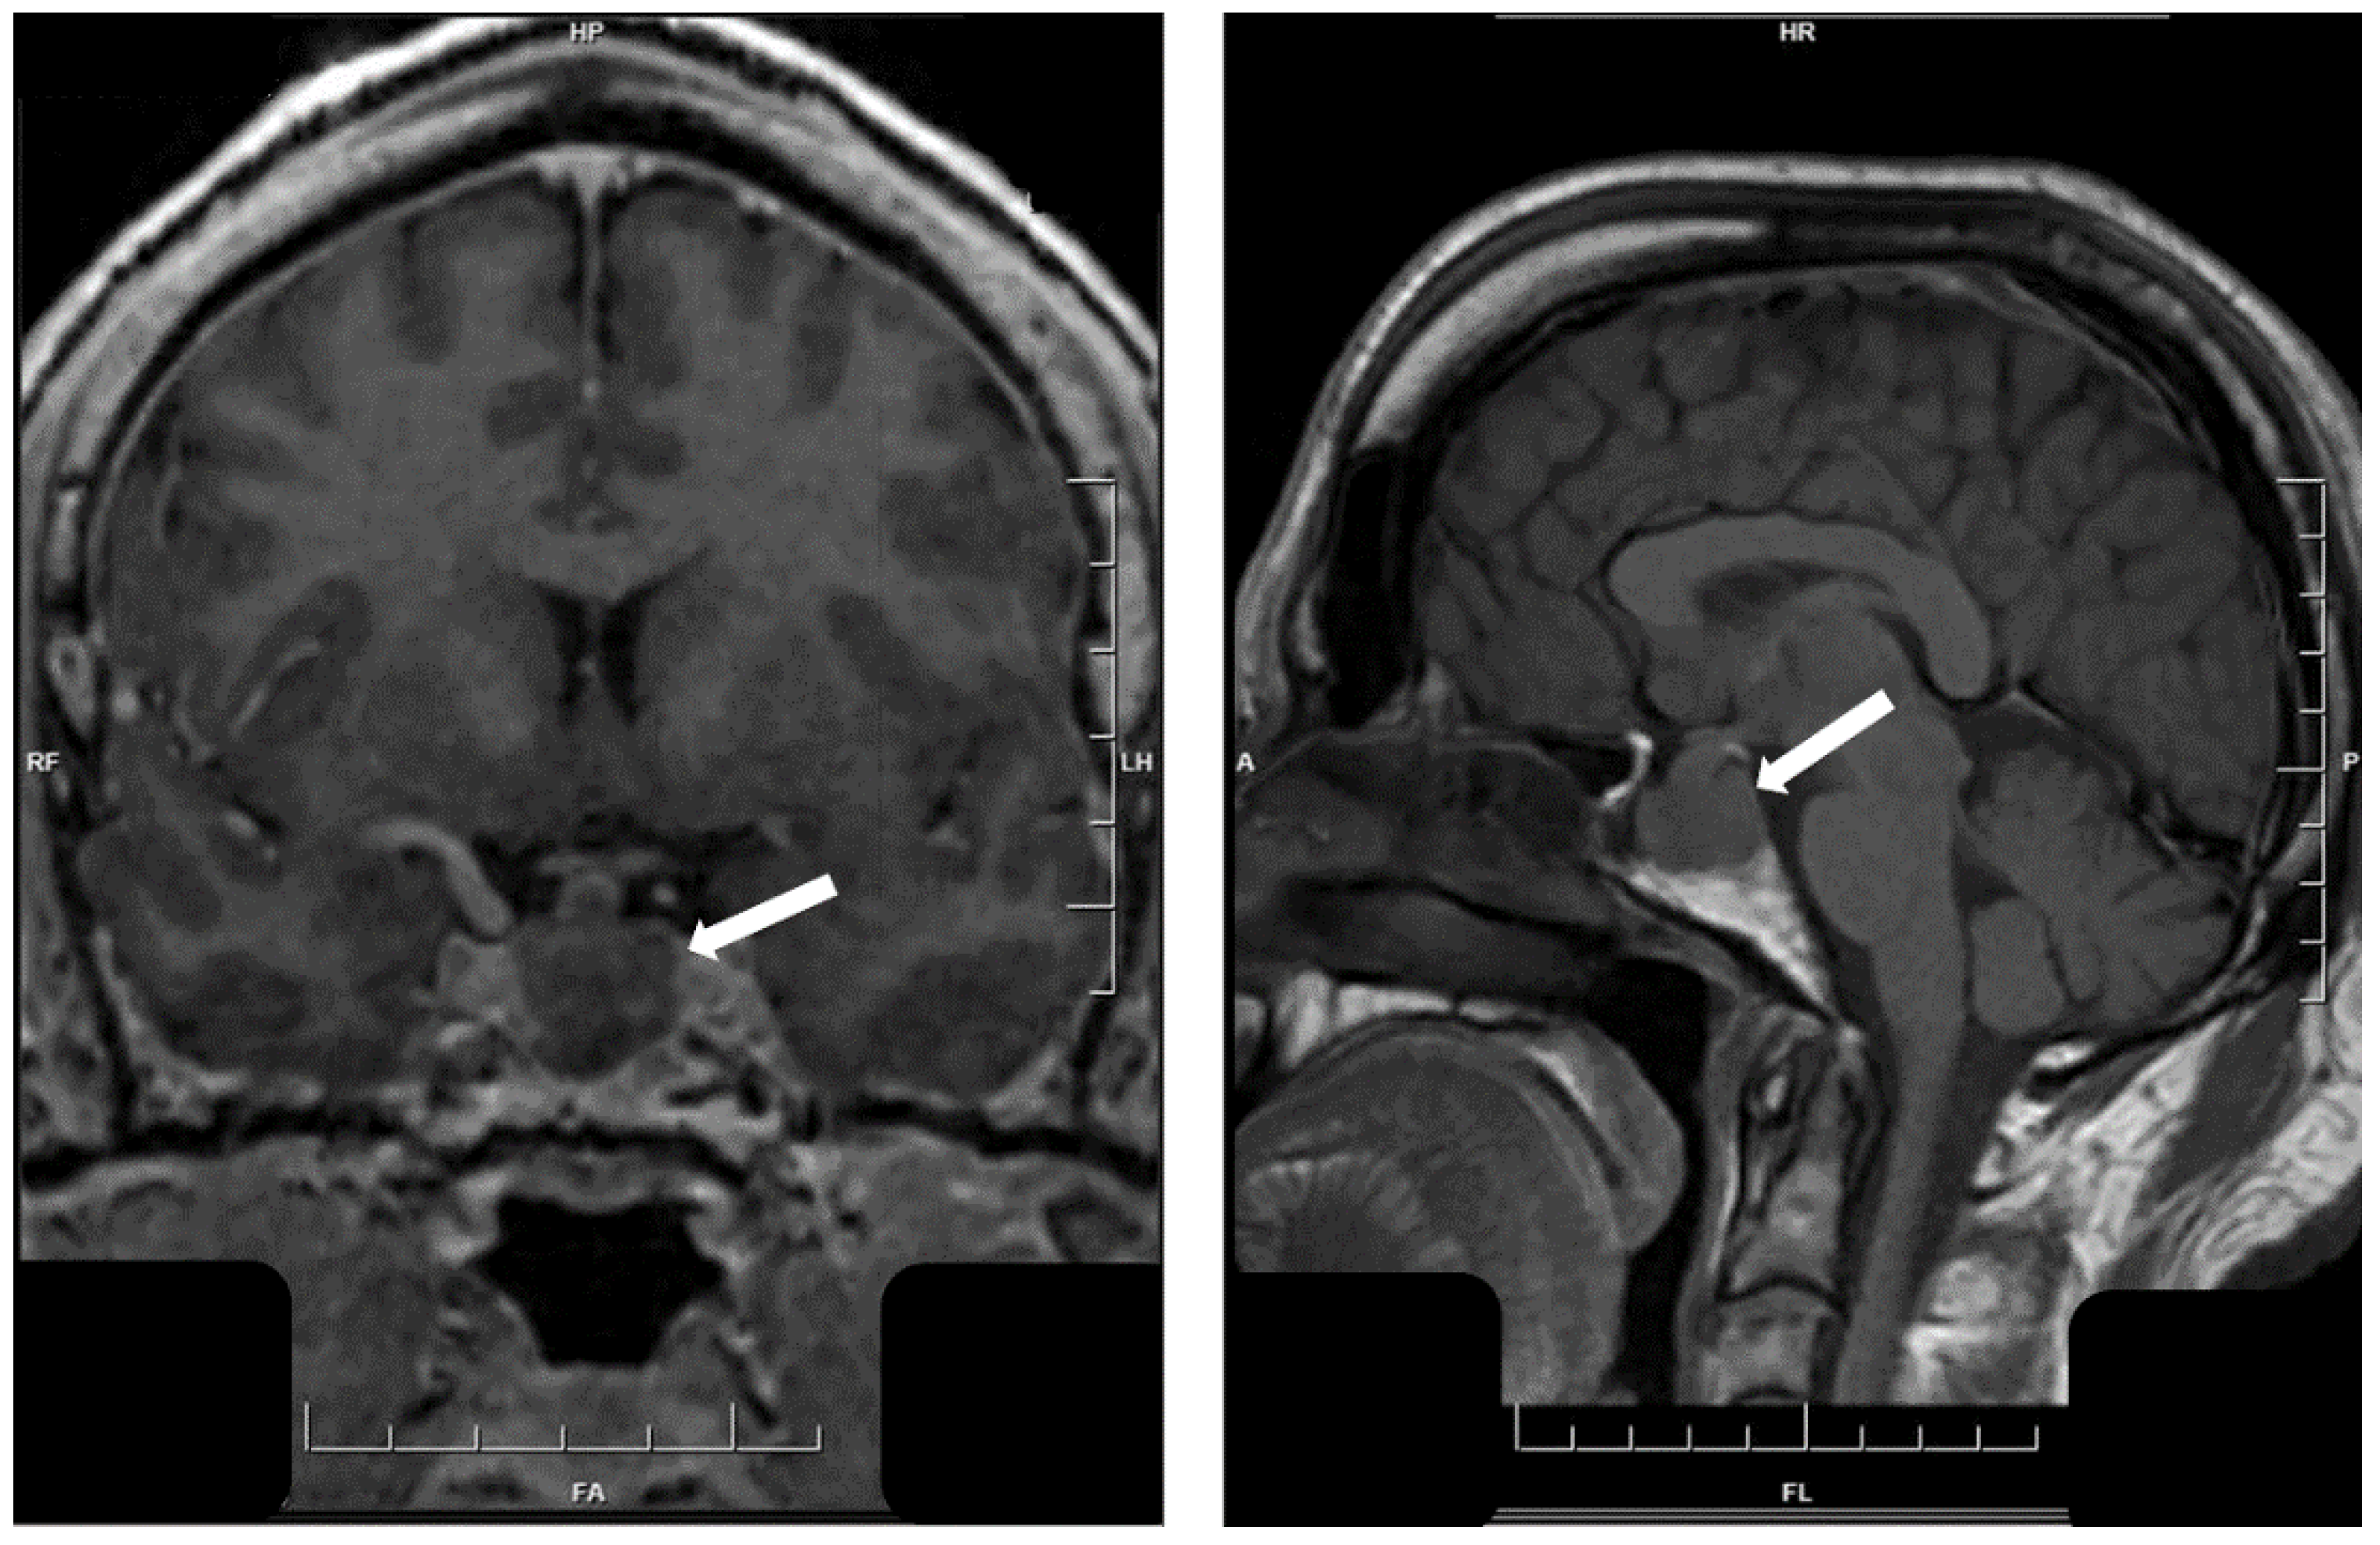

- Asa, S.L.; Kucharczyk, W.; Ezzat, S. Pituitary acromegaly: Not one disease. Endocr. Relat. Cancer 2017, 24, C1–C4. [Google Scholar] [CrossRef] [PubMed]

- Heck, A.; Ringstad, G.; Fougner, S.L.; Casar-Borota, O.; Nome, T.; Ramm-Pettersen, J.; Bollerslev, J. Intensity of pituitary adenoma on T2-weighted magnetic resonance imaging predicts the response to octreotide treatment in newly diagnosed acromegaly. Clin. Endocrinol. (Oxf.) 2012, 77, 72–78. [Google Scholar] [CrossRef]

- Potorac, I.; Petrossians, P.; Daly, A.F.; Alexopoulou, O.; Borot, S.; Sahnoun-Fathallah, M.; Castinetti, F.; Devuyst, F.; Jaffrain-Rea, M.L.; Briet, C.; et al. T2-weighted MRI signal predicts hormone and tumor responses to somatostatin analogs in acromegaly. Endocr. Relat. Cancer 2016, 23, 871–881. [Google Scholar] [CrossRef] [PubMed]

- Akirov, A.; Asa, S.L.; Amer, L.; Shimon, I.; Ezzat, S. The clinicopathological spectrum of acromegaly. J. Clin. Med. 2019, 8, 1962. [Google Scholar] [CrossRef]